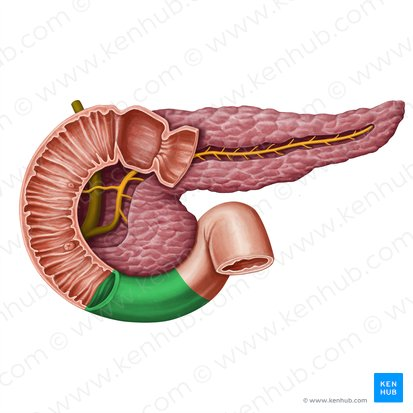

Duodenum

This is the first and shortest segment of the small intestine. It receives partially digested food (known as chyme).

Receives digestive enzymes from the pancreas and bile from the liver and gallbladder through the pancreatic and bile ducts.

Pancreas

A gland located behind the stomach that produces digestive enzymes and hormones like insulin and glucagon.

Pancreatic Duct

A duct that carries digestive enzymes produced by the pancreas to the duodenum. It typically joins with the bile duct before entering the duodenum.

Bile duct

A duct that carries bile produced by the liver and stored in the gallbladder to the duodenum, where it aids in the digestion of fats.

Major Duodenal Papilla

An opening in the wall of the duodenum where the common bile duct and the pancreatic duct typically enter to deliver bile and pancreatic enzymes.

Pancreatic Duct / Duct of Wirsung

The main duct that runs through the length of the pancreas, collecting digestive enzymes from the pancreatic cells and transporting them to the duodenum.

Accessory Pancreatic Duct / Duct of Santorini

A smaller pancreatic duct that branches off the main pancreatic duct and may also empty into the duodenum, usually superior to the major duodenal papilla.

Hepatopancreatic Ampulla / Ampulla of Vater

A dilated chamber formed by the joining of the common bile duct and the pancreatic duct before they enter the duodenum.

Sphincter of Hepatopancreatic Ampulla / Sphincter of Oddi

A muscular valve that surrounds the hepatopancreatic ampulla and controls the flow of bile and pancreatic juice into the duodenum.

Major Duodenal Papilla

The raised opening in the wall of the duodenum where the hepatopancreatic ampulla typically empties its contents.

Mucosa of Duodenum

The inner lining of the duodenum, which contains specialized cells for absorption and secretion.